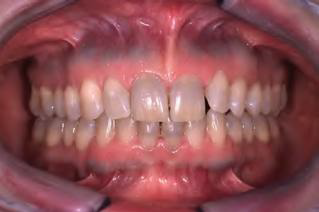

Eruption cyst (EC) | Dentigerous 萌發 | 12a, 12b, 34a, ?6 | 10y ↓ | 藍色或紫棕色 ![]() ![]() |